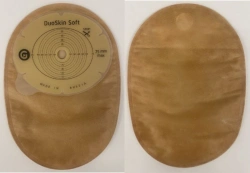

Medical product is intended for use in colostomies, ileostomies and urostomies for hermetic and secure attachment of stoma bags to the skin of the anterior abdominal wall, as well as to protect the skin of the peristomal area from stoma secretions and preserve the physiological functions of the skin due to the absorption of natural skin moisture (sweat, sebum).